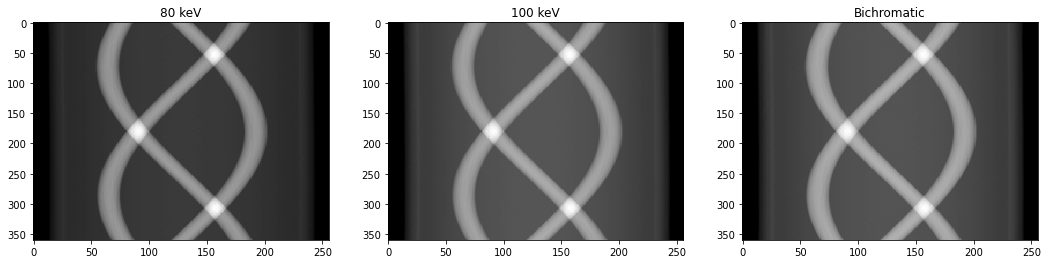

On se propose de simuler une acquisition polychromatique, c’est-à-dire, une acquisition issue d’un faisceau de rayons X distribué sur plusieurs énergies. Le plus simple est de considérer une approximation bichromatique du faisceau. Dans ce contexte, on considère que les photons X incidents sont de deux énergies, à savoir 80 keV et 100 keV. La probabilité que le photon incident soit à 80 keV est donnée par $P(80) = a_{80}$, et celle d’avoir un photon incident à 100 keV est $P(100)=1-P(80)$.

# Question 4

def bichromatic(p,a80=0.66):

pixel2cm = 0.1

return -np.log(a80*np.exp(-pixel2cm*p[80]) + (1 - a80)*np.exp(-pixel2cm*p[100]))/pixel2cm

a80 = 0.66

sinogram = bichromatic(p,a80)

fig, ax = plt.subplots(1,3,figsize=(18,4))

ax[0].imshow(p[80].T)

ax[0].axis('auto')

ax[0].set_title('80 keV')

ax[1].imshow(p[100].T)

ax[1].axis('auto')

ax[1].set_title('100 keV')

ax[2].imshow(sinogram.T)

ax[2].axis('auto')

ax[2].set_title('Bichromatic')

plt.show()